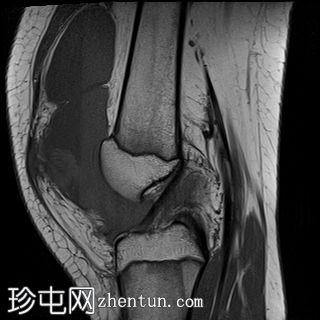

矢状位

T1加权像

PD脂肪抑制序列

关节内大量积血,可见血细胞比容增高征。股骨外侧髁前部及髌骨内侧可见挫伤性微骨折。髌骨内侧支持带及髌股内侧韧带水肿增厚。髌骨内侧关节面下关节软骨浸润,提示I期骨软骨损伤。

髌骨外侧隐窝可见游离体,其信号强度与关节软骨一致,提示髌骨关节软骨外剥离损伤。股骨滑车和股骨关节软骨正常。

胫骨近端和腓骨骨骺以及股骨远端延伸至干骺端的骨骺周围可见局灶性骨髓水肿。这些提示存在局灶性骨骺周围水肿区。

十字韧带和侧副韧带正常。半月板正常。股四头肌腱和髌腱正常。

该病例具有短暂性髌骨外侧脱位复位损伤的特征性表现,包括预期的骨挫伤模式、内侧髌骨支持带/内侧髌股韧带损伤、髌骨骨软骨损伤以及髌骨软骨游离体。